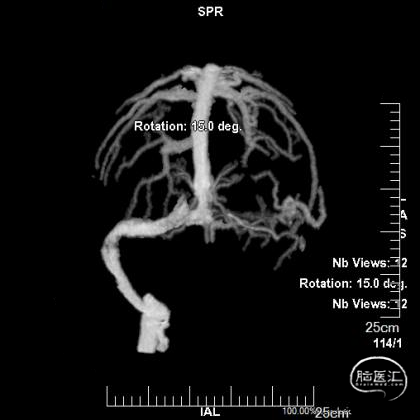

术前CTV:左侧颈内静脉、乙状窦、横窦闭塞,血栓形成。

术前MRV提示血栓负荷不断增加。

术前复查MRV提示血栓累及范围继续扩大。

经中间管手推造影,确认血栓位置。